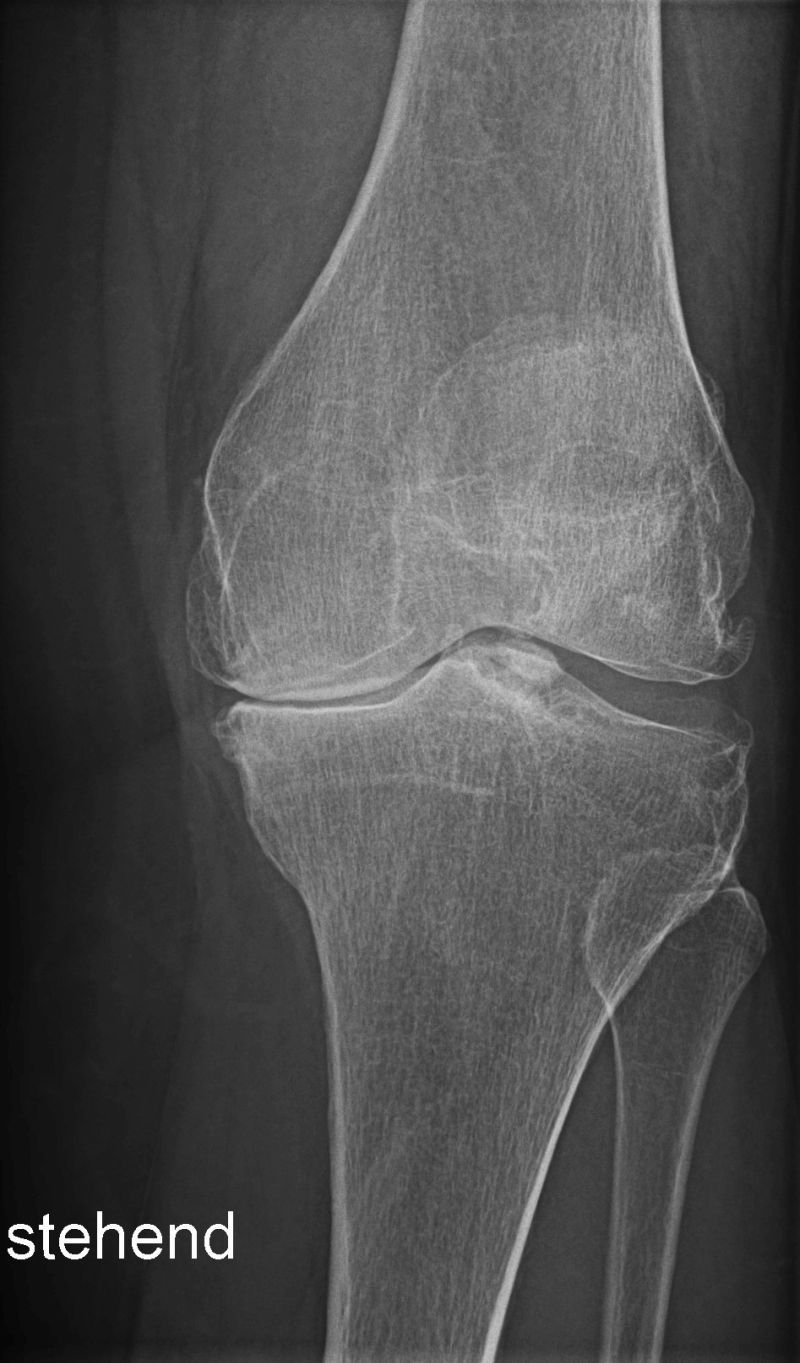

Röntgen des Skeletts und der Gelenke

Das Röntgen hat in der Orthopädie und Unfallchirurgie nach wie vor einen hohen Stellenwert. So können z.B. Knochenbrüche z.B. nach Unfall oder bei Osteoporose gefunden oder ausgekugelte Gelenke festgestellt werden. Ohne viel Zeit zu verlieren kann dann eine für Sie optimale Therapie begonnen werden. Auch das Ausmaß von Verschleißerscheinungen, die Arthrose, kann mit dem Röntgenbild festgestellt werden. In der Rheumatologie werden die Gelenke - meist Hände und Füße - geröngt, um das Ausmaß der entzündlichen Veränderungen am Knochen beurteilen zu können.